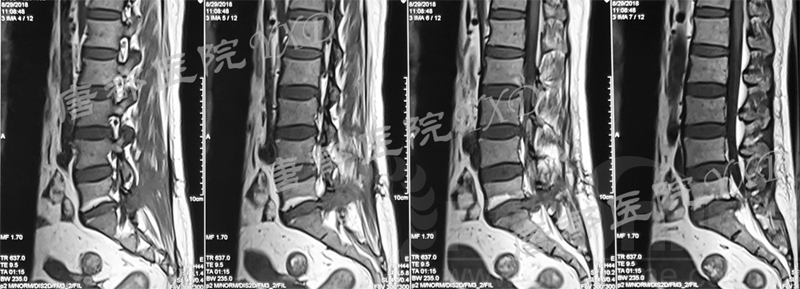

影像学检查:

诊断:腰椎间盘突出症术后复发

手术方案:显微镜辅助MI-TLIF腰椎翻修术

术中视频:http://api.orthonline.com.cn/attach/Case2.mp4(术中发现因前三次侧路及后路内镜手术的操作,术区大量瘢痕组织增生、与神经粘连严重;此外,摘除头侧游离髓核时连接有软骨终板脱落;在显微镜操作下,安全地将神经进行充分松解,压迫神经的游离髓核及软骨终板彻底清除。无手术并发症)